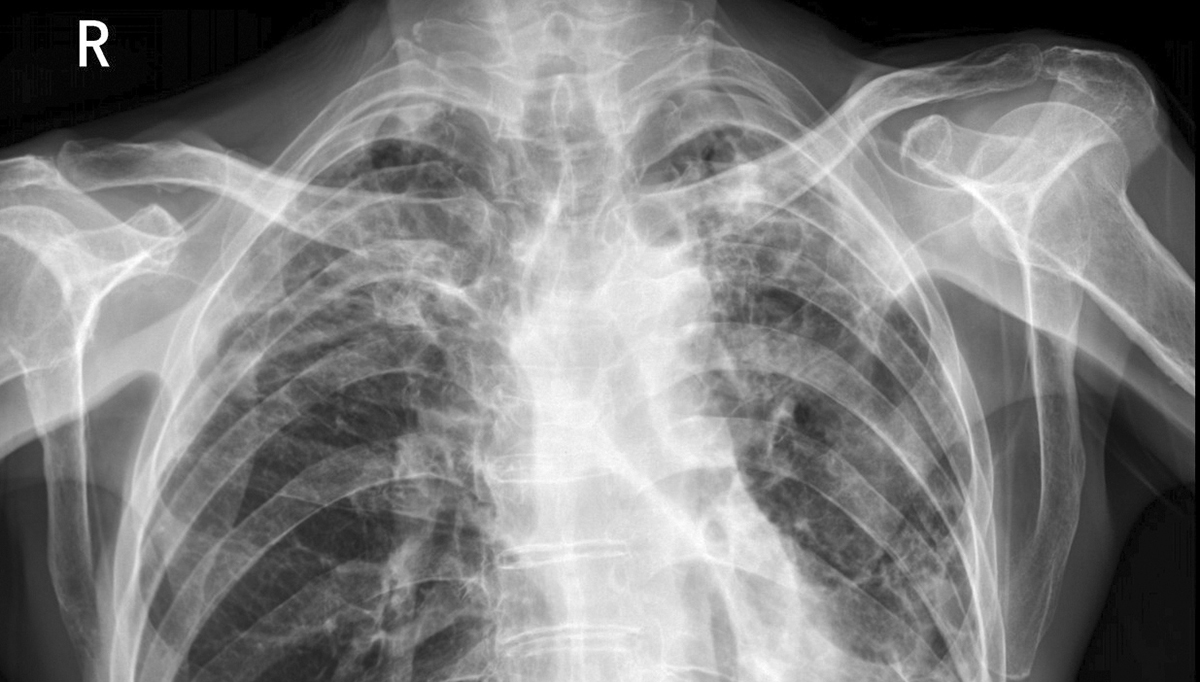

医学影像中,早期肿瘤、微小钙化点等病灶常表现为灰度差异极小的区域。医用诊断显示器的高等级灰阶响应能确保这些细微亮度变化被精准呈现,避免因灰阶过渡不连贯导致病灶遗漏。例如在胸部 CT 影像中,1024 级灰阶结合快速灰阶响应,可清晰区分正常组织与早期结节的灰度差异。